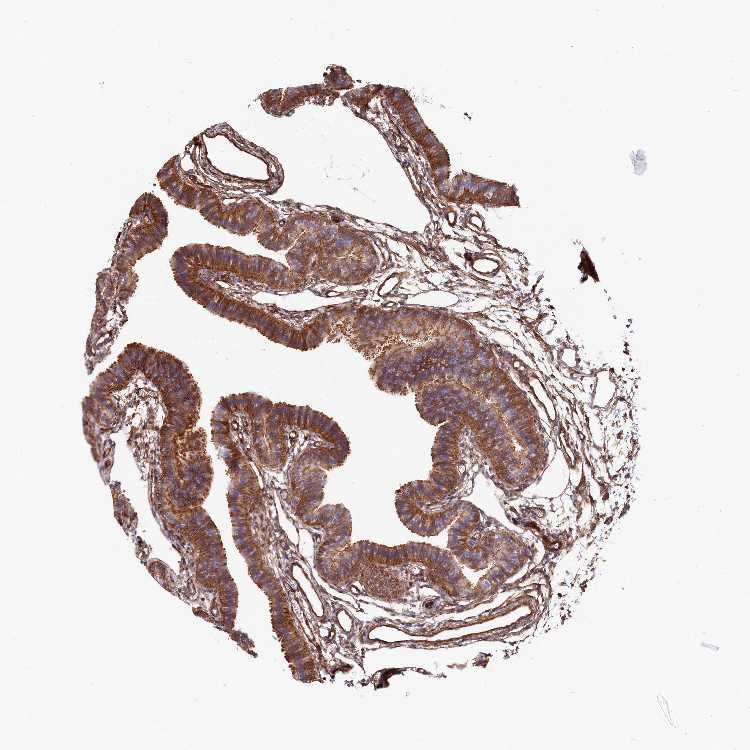

TISSUE PRIMARY DATA FALLOPIAN TUBE Show tissue menu

Fallopian tube

FALLOPIAN TUBE - Expression summary

FALLOPIAN TUBE - Antibody stainingi

Antibody staining in the annotated cell types in the current human tissue is reported as not detected, low, medium, or high, based on conventional immunohistochemistry profiling in selected tissues. This score is based on the combination of the staining intensity and fraction of stained cells.

Each image is clickable and will lead to virtual microscopy that enables deeper exploration of all samples and also displays staining intensity scores, fraction scores and subcellular localization as well as patient and tissue information for each sample.

Antibody HPA037929Antibody HPA037930

Glandular cells HighHigh